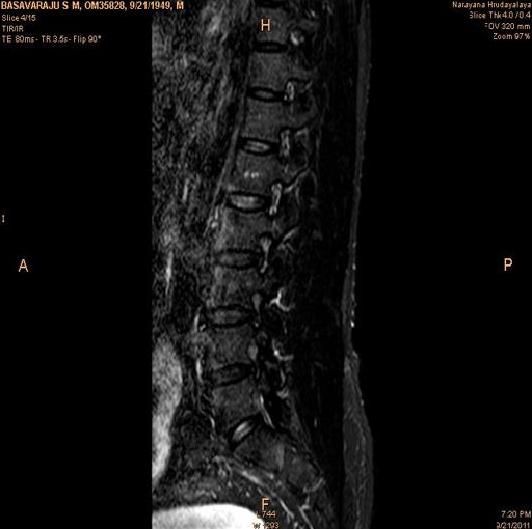

In order to show the proposed method in more detail, the algorithm is tested with other test images. The first row of Fig. 6 shows the original MRI image of thoracic spine with different views. The second row of Fig. 6 shows the same image enhanced using histogram equalization. Third row of Fig. 6 presents the MSR based enhancement scheme. Fourth row of Fig. 6 indicates Chao’s method of image enhancement. Finally, the reconstructed images using the proposed method is shown in fifth row of Fig. 6. Again, it can be seen from the results presented that the image enhancement using the proposed method is superior compared to other methods. This is evident from the image quality assessment presented in Table 1 using AWE and DWE.